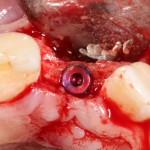

Другой вариант. Имплантируем, но существующего объема костной ткани недостаточно для получения адекватного эстетического и функционального результата:

Поэтому мы используем мембрану Geistlich BioGide и всё ту же аутокостную стружку:

Вот чем мне нравится мембрана BioGide — так это своими свойствами. Предсказуема до мелочей.

Во влажном состоянии она эластична и податлива, поэтому нет необходимости использовать пины или винты:

ну и, швы: